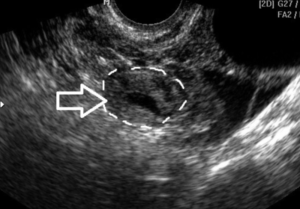

При трансвагинальной методике, при условии скопления достаточного количества жидкости в малом тазу, иногда удается «поймать» этот орган. Нормальные трубы имеют однородную структуру; мышечный слой и просвет не определяются. В некоторых случаях врач может увидеть ампулярный сегмент с фимбриями.

В норме маточные трубы при процедуре ультразвукового исследования не визуализируются. Это означает, что их не видно. Разглядеть их на УЗИ можно в том случае, когда происходит скопление жидкости в просвете фаллопиевых труб. А это признак воспалительного процесса, то есть патология.

Кроме воспалительных процессов в маточных трубах может развиваться и спаечный процесс. В этом случае, если просвет трубы закрыт полностью, образуется сактосальпинкс и гидросальпинкс – полость, заполненная жидкостью. Характер жидкости можно установить при дальнейшем обследовании, а УЗИ установит наличие воспалительного процесса, локализацию (правая и/или левая труба).